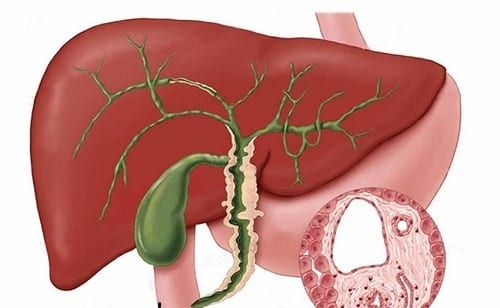

La colangitis biliar primaria es una enfermedad hepática autoinmune caracterizada por la destrucción progresiva de los conductos biliares intrahepáticos que conduce a la colestasis. Esto conduce a la fibrosis, que puede provocar cirrosis e insuficiencia hepática.

El diagnóstico de colangitis biliar primaria se puede establecer cuando se cumplen dos de los siguientes tres criterios:

- evidencia bioquímica de colestasis basada principalmente en la elevación de la fosfatasa alcalina

- presencia de anticuerpo antimitocondrial

- evidencia histológica de colangitis destructiva no supurativa y destrucción de los conductos interlobulillares.